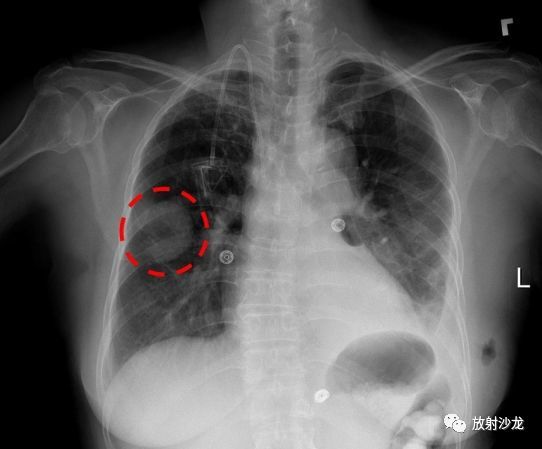

人工智能正在颠覆几乎所有可以想象的领域,运输、金融、教育等等。最近,人工智能将瞄准的一个关键领域是医疗保健,将改变诸如个性化医疗、临床决策甚至医疗保险等领域。 也许人工智能能够最快改变的医疗领域就是放射领域。人工智能将是解读重要医学影像的关键,这些医学影像反映我们身体内部的情况,例如CT扫描、MR和X射线图像,帮助医生做好他们最擅长的事:诊断。 为什么放射领域会成为第一个被人工智能彻底革新的医学领域?什么是让医学成像领域被深度学习的魔力折服呢? 1. 放射学是可视的。医学扫描当然是可视的,而人工智能在分析视觉图像方面尤其强大——这至少部分归功于人工智能技术在安全和社交媒体服务中取得的突破,它可以识别我们的面孔并从人群中找到我们。 放射领域高度依赖对视觉数据的解释,这使得它比其他一些医学领域更适合深度学习技术。这意味着,放射科医师可以立即从人工智能技术的使用中受益,而精神病医生或胃肠病专家则不能。 2. 放射科被行业急需。医学影像(CT和MR)的数量持续大幅度增加——它们在2016年所有检测中分别占到了7.9%和8.9%。然而,在进行了更多扫描的同时,放射科医师的数量已经进入了稳定阶段。而且,随着技术的进步,每次扫描的分辨率和图像数量呈指数级增长。因此,需要考虑的细节数量也相应地增加了。这就产生了巨大的技术需求,这种技术可以突破日益增长的工作负荷造成的危险瓶颈——而且,正如我们所知,需要是发明之母,深度学习可以帮助评估CT和MRI扫描结果,快速找出放射科医师应该重点关注的区域,以便他们进一步进行检查,同时还允许更快地评估紧急扫描——因此改善了患者的预后。 3. 放射科是以技术为中心的。除了其视觉本质之外,放射科已经是一个以技术核心的领域。放射科医生每天都依赖大量先进技术——每次检查都涉及到各种先进的软件系统、诊断监视器和工作站, 由于他们日常工作的技术驱动性质,放射科医生被认为是“早期采用者”。这就是为什么他们更有可能采用由人工智能支持的其他技术,而早期也有例子表明,放射科医生比其他许多同事更善于接受创新:80年代的放射科接受了从胶片到数字图像的转变。 4. 有大量可供使用的数据。所有的深度学习都需要大量的数据才能真正有效,对于放射学来说,这些数据的存在形式是过去几十年针对各种症状积累的无穷无尽的影像。 当 然,数据的挖掘也存在挑战,挑战在于人工智能算法如何获取这些影像。而最近,一些医疗机构公开分享他们的匿名数据催生了这一领域的热潮,比如,美国国家卫生研究院(National Institutes of Health)最近公布的X射线数据集,该数据集包含了超过100,000张带有注释的图像(如下图)。